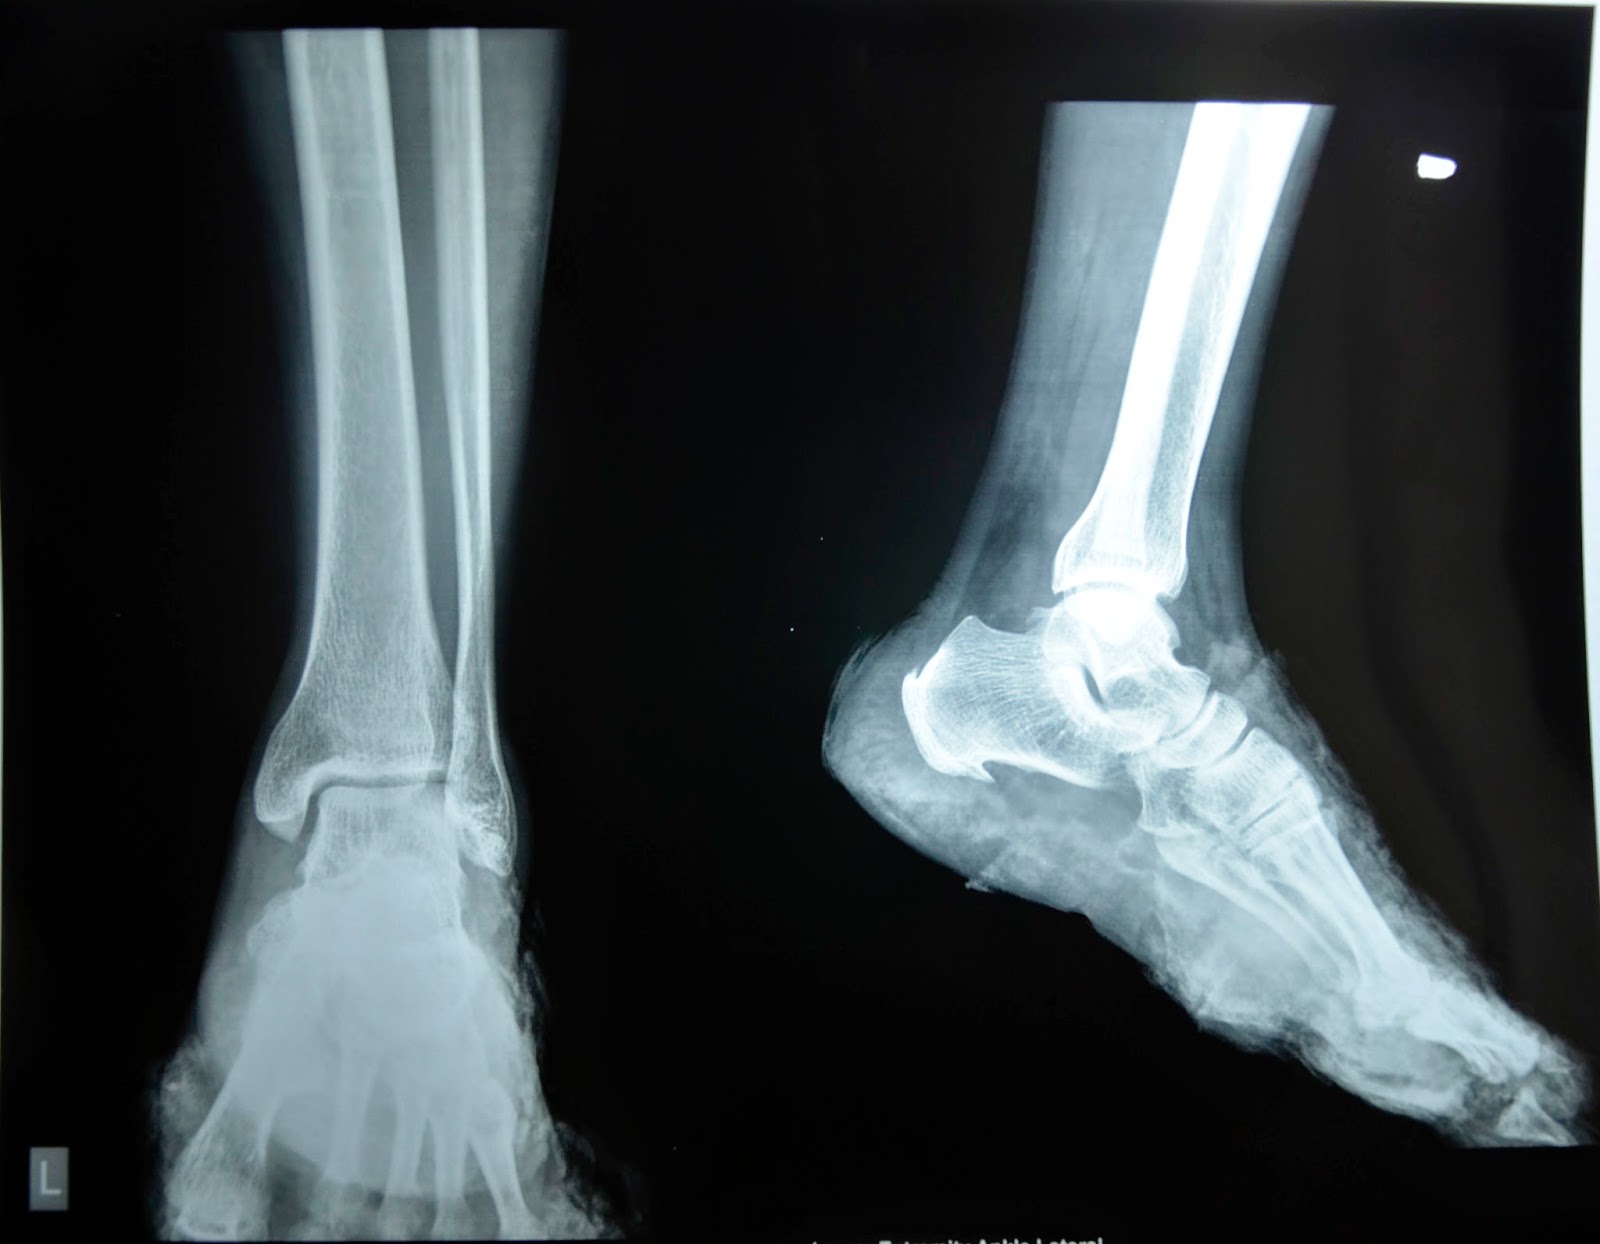

From radiopaedia.org

Xray Interpretation Foot and Ankle Injuries Foot Pain After Crush Injury If your foot crush injury has excessive swelling, pain, or bleeding, you will need to see a doctor for treatment. People that have suffered crush injuries of the foot often complain of stiffness, soreness, or inability to perform activities after an extended period of time. The physician will perform a. Foot crush injuries are more severe than regular foot fractures.. Foot Pain After Crush Injury.